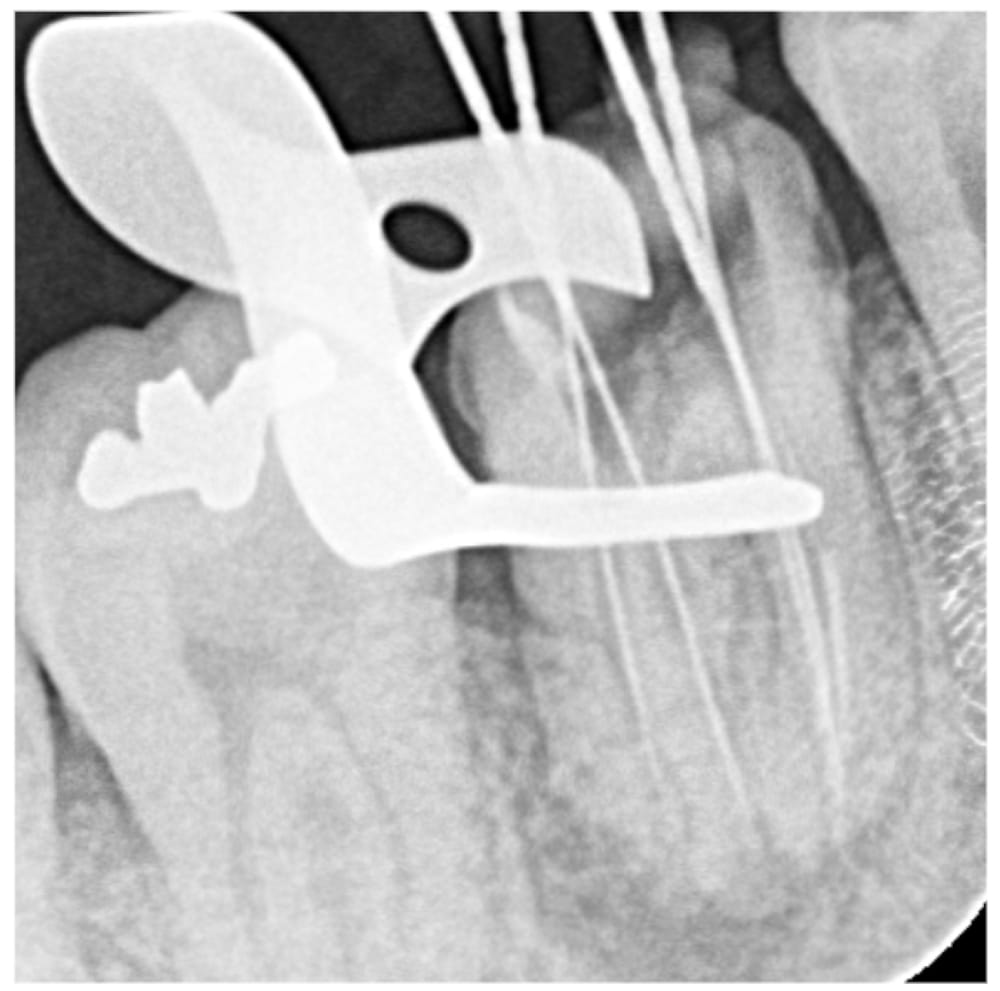

根の先の膿が大きく、歯茎も腫れている状態でした。過去の根管治療ではラバーダムは使用されておらず、根管充填の質もPoorであることから、再根管治療を行うことになりました。

根管は4根管があり、過去の充填材料を除去する必要がある点、根管内の感染が強い点から、根管貼薬を行う2回法で処置を行いました。治療は問題なく完了しましたが、残存歯質量に不安があり、長期予後はQuestionableな状態でした。レジンにてコア築造を行い、6ヶ月後の経過観察となりました。